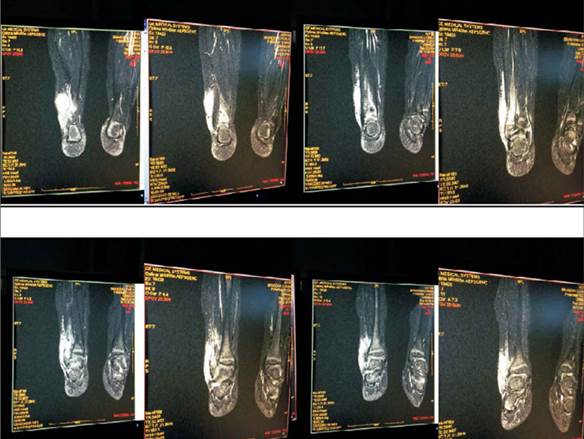

A las 72 horas del ingreso se realiza resonancia nuclear magnética (RNM) de tobillo derecho: en T1 en tercio inferior del peroné e interlínea articular tibiotarsiana imágenes hipointensas, lesión en astrágalo con imagen en sacabocado. En T2 imágenes hiperintensas (Figura 2, Figura 3 y Figura 4).